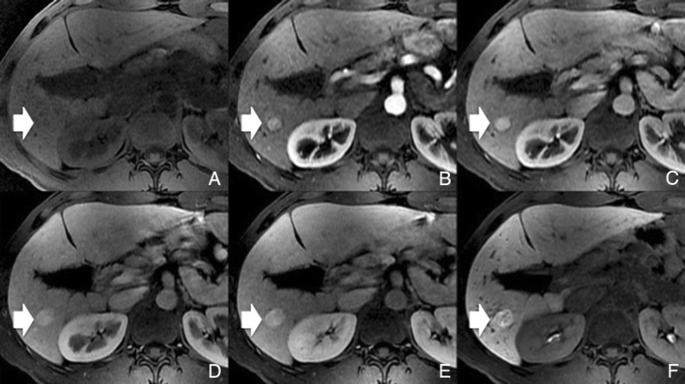

Fig. 3 A benign cirrhosis-associated nodule in a 39-year-old man with chronic liver disease. Gd-EOB-DTPA enhanced MRI. a arterial phase, b PV phase, c delayed phase, d 5 min, e 10 min, f hepatocellular phase. The image shows a liver with a nodular contour and a heterogeneous parenchyma. The arrows point to a small rounded focal lesion accumulating Gd-EOB-DTPA- benign nodule

Potential pitfalls: Siderotic and steatotic nodules may appear hypointense in the HCP, potentially mimicking early HCC. This is due to the iron and fat content being already of low signal intensity in the pre-contrast fat saturated sequences. Some benign nodules may appear hyperintense in the HCP [14] (Fig. 3). The mechanism is still unknown, but overexpression of organic anionic transporter peptides (OATP) or down-regulation of MDRs could possibly play a role. Such lesions may be mistaken for focal nodular hyperplasia (FNH)-like lesions (these are also benign, so the distinction is irrelevant) or atypical HCCs with HCP hyperintensity. The differentiation between benign and malignant HCP-hyperintense nodules is discussed in the following two sections. Small benign cirrhosis-associated nodules with arterial-phase hyperenhancement and HCP hypointensity may be indistinguishable from small HCCs.